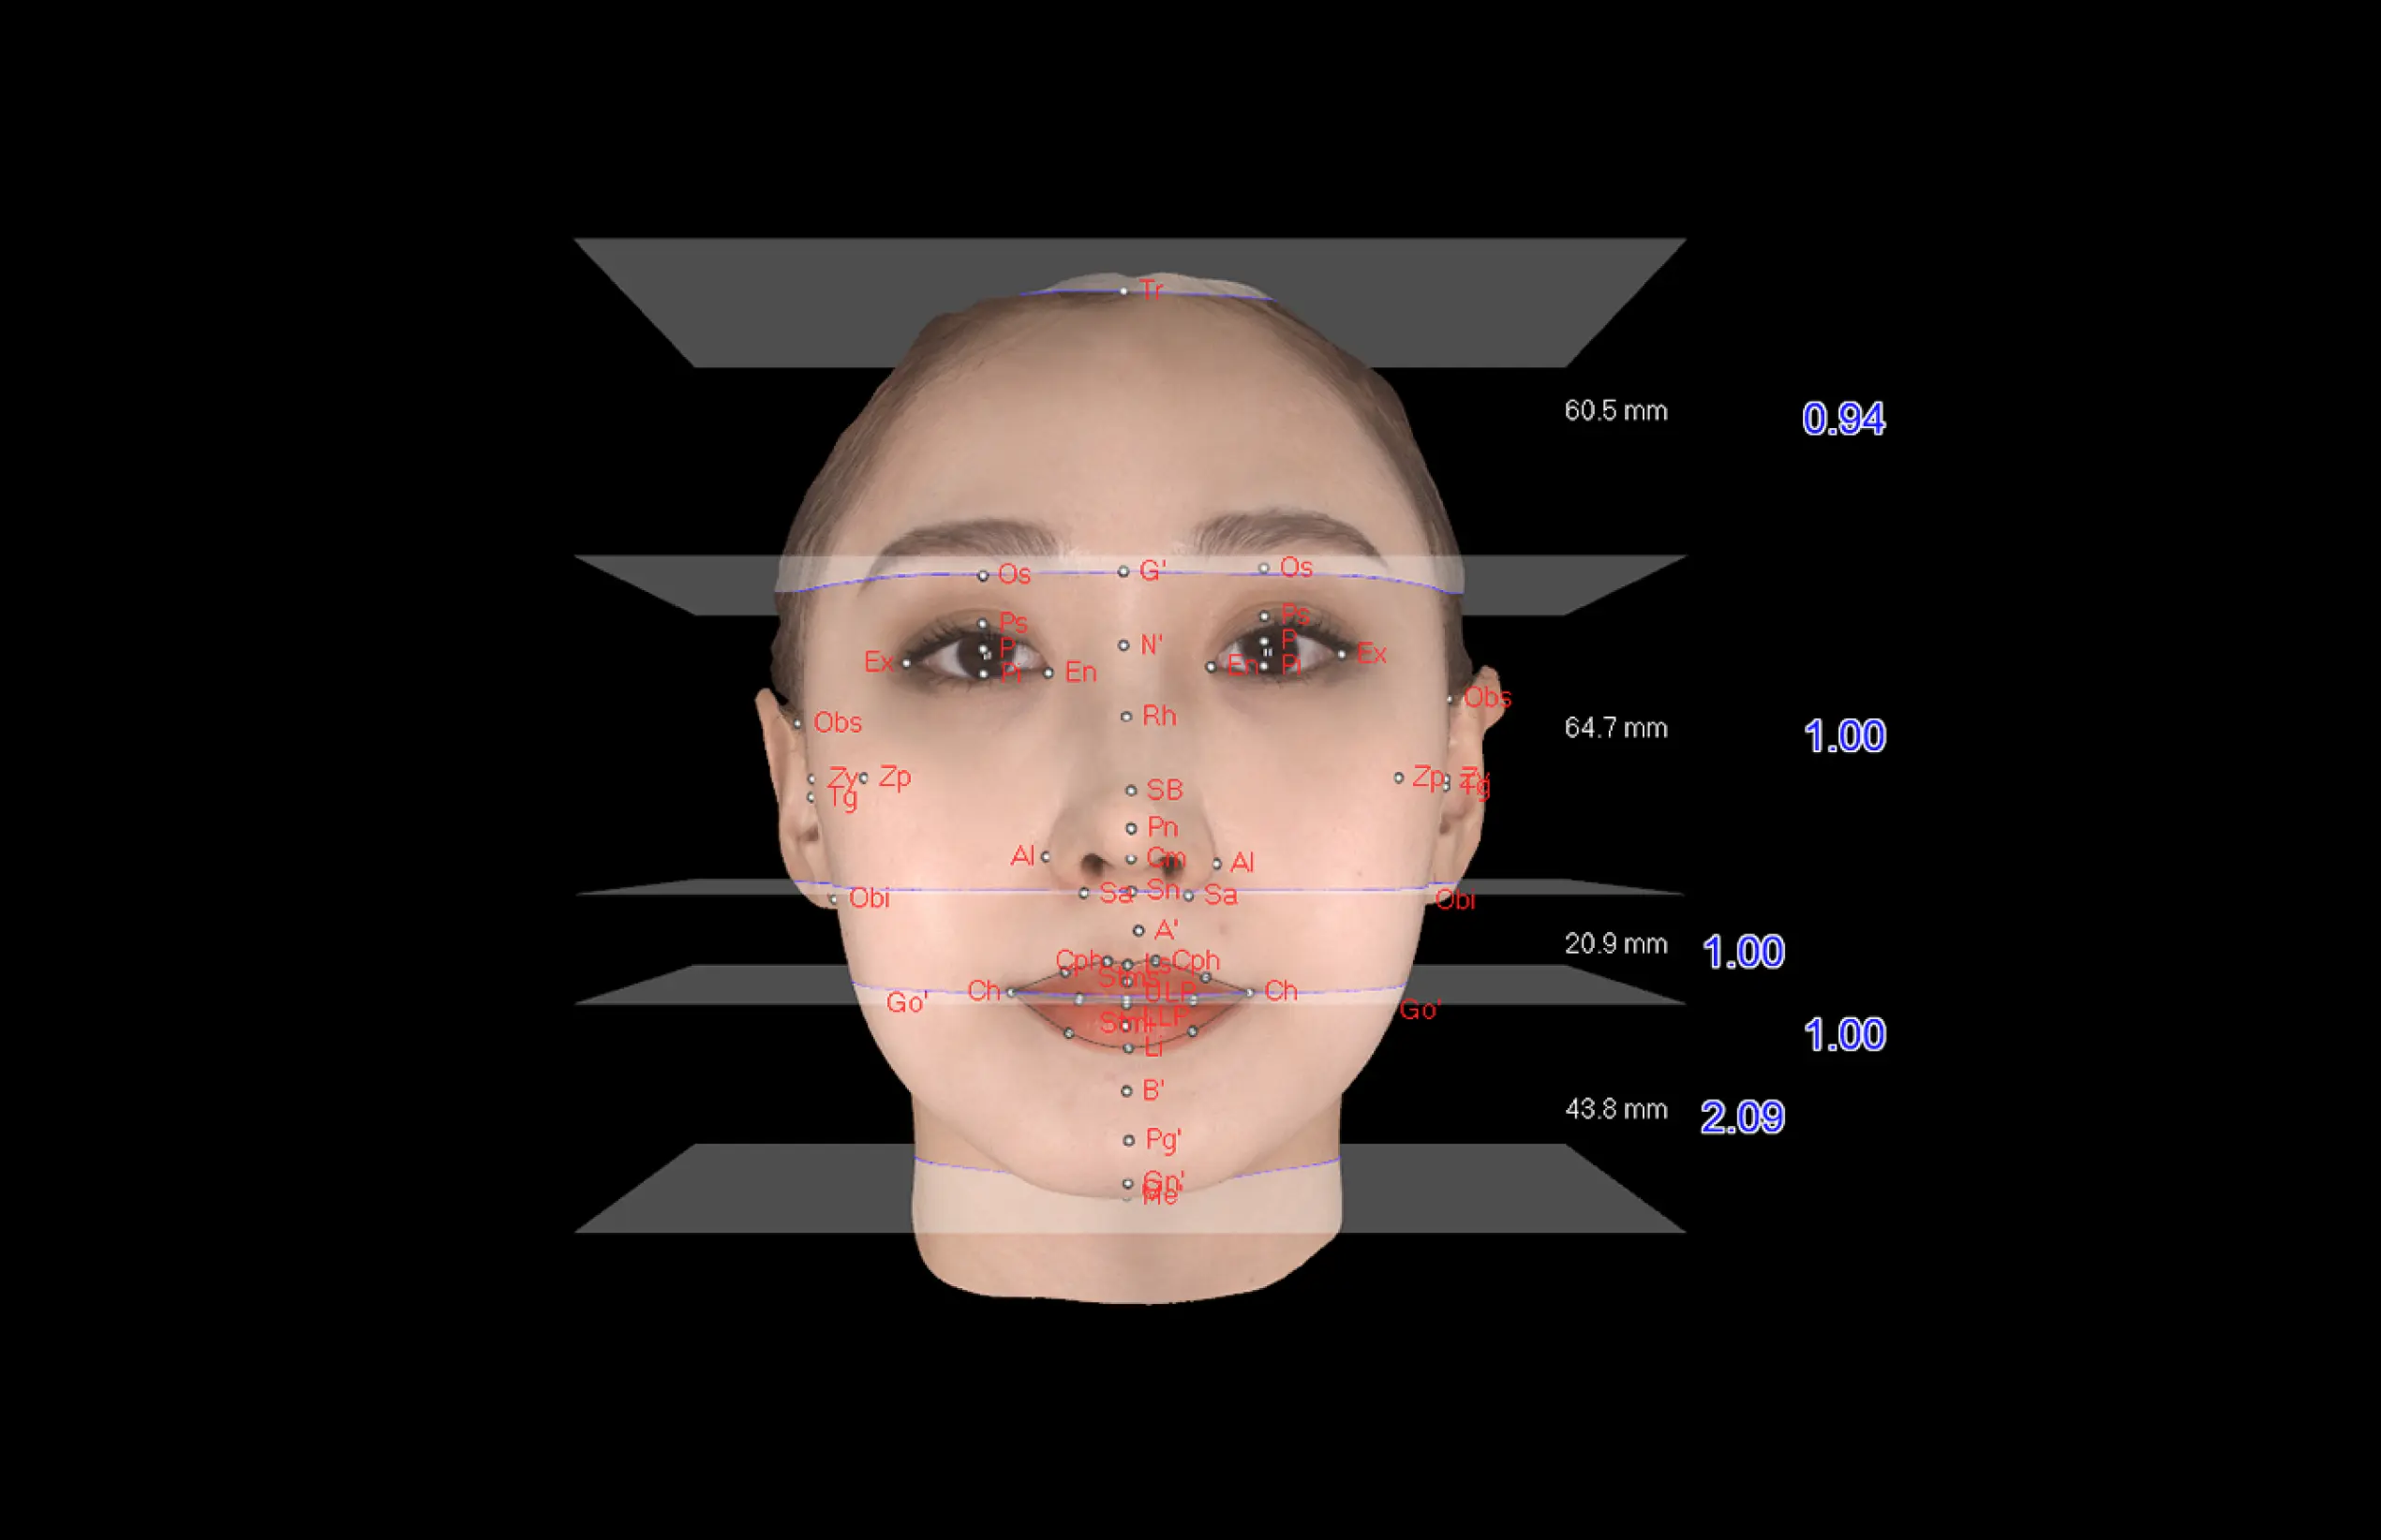

더보기 눈과 미간의 균형

·얼굴 상안, 중안, 하안의 직선 너비

·안각간 거리와 좌·우안 거리의 비율을 측정

하는 수평적 분석